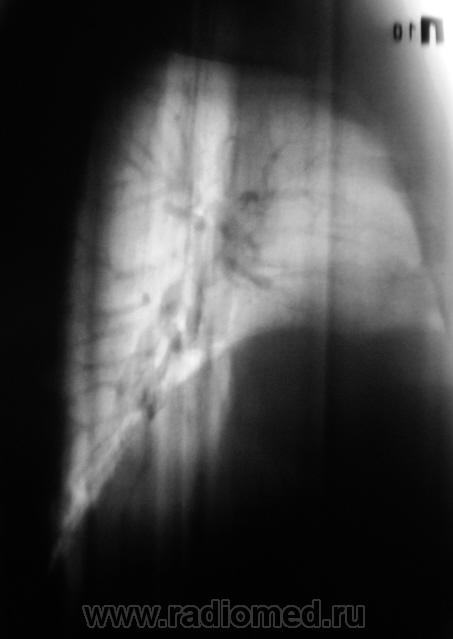

Пациент, после анализа флюорограмм "взят на контроль". Произведено стандартное дообследование - рентгенография в прямой и правой боковой проекциях, боковая томография. По большому счету, пациет жалоб не предъявляет.

Вначале думал о центральном раке, ателектазе, но на томограммах видно четко бронхи "воздушная бронхограмма". Может пневмония?.

Массивное затемнение "вне анатомических границ", рождает сомнения по поводу "осумкования". Что за снижение прозрачности "сзади", но фоне чего хорошо дифференцируется бронх - думаю, что "инфильтрация". пациент в стационаре, назначена противовоспалительная терапия. По всей видимости, динамика будет выставлена, если "область не заберет на себя".

Мыслей о междолевом осумкованном плеврите нет, т.к. контуры не ровные, о центральном раке не думаю т.к. бронхи говорят об их интактности, думаю пока о пневмонии. Динамика в данном случае, в паре с лечением должа дать ответ.